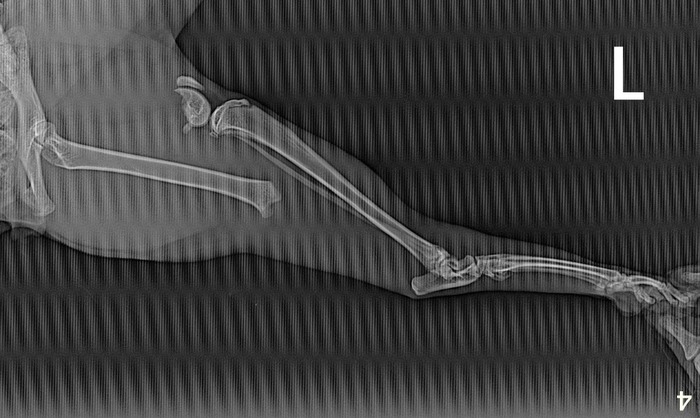

Но тем не менее у данной породы есть генетические проблемы с позвоночником и задними конечностями. Как сообщил ветеринар:

"Дисплазия ТБС может быть, действительно, без рентгена это не от диагностировать, также возможны и другие патологии пояснично-крестцового отдела позвоночника вызывающие сходную симптоматику"

К сожалению рентген ему сейчас не сделать, т.к. он не набрал свой вес, а с истощением нельзя давать ему седативные (а без них рентген не сделать).

Но это не срочная процедура, поэтому ждет.